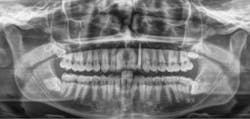

Figure 1a: Pre-op panorex

Figure 5: Post-op panorex

Figure 7: Pre-op panorex